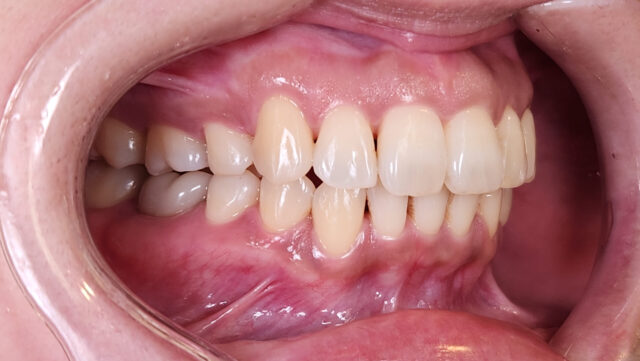

After

矯正完了後